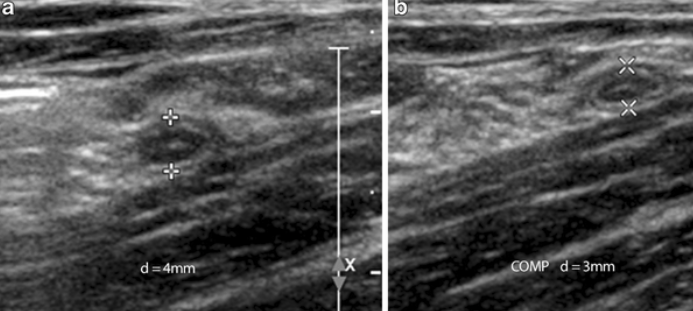

초음파 소견: tubular wall thickening - Appendiceal diameter > 6mm (진단적), noncompressible (배를 눌렀을 때 충수돌기가 눌리지 않음), 도플러 혈류 증가

normal appendix의 초음파 소견